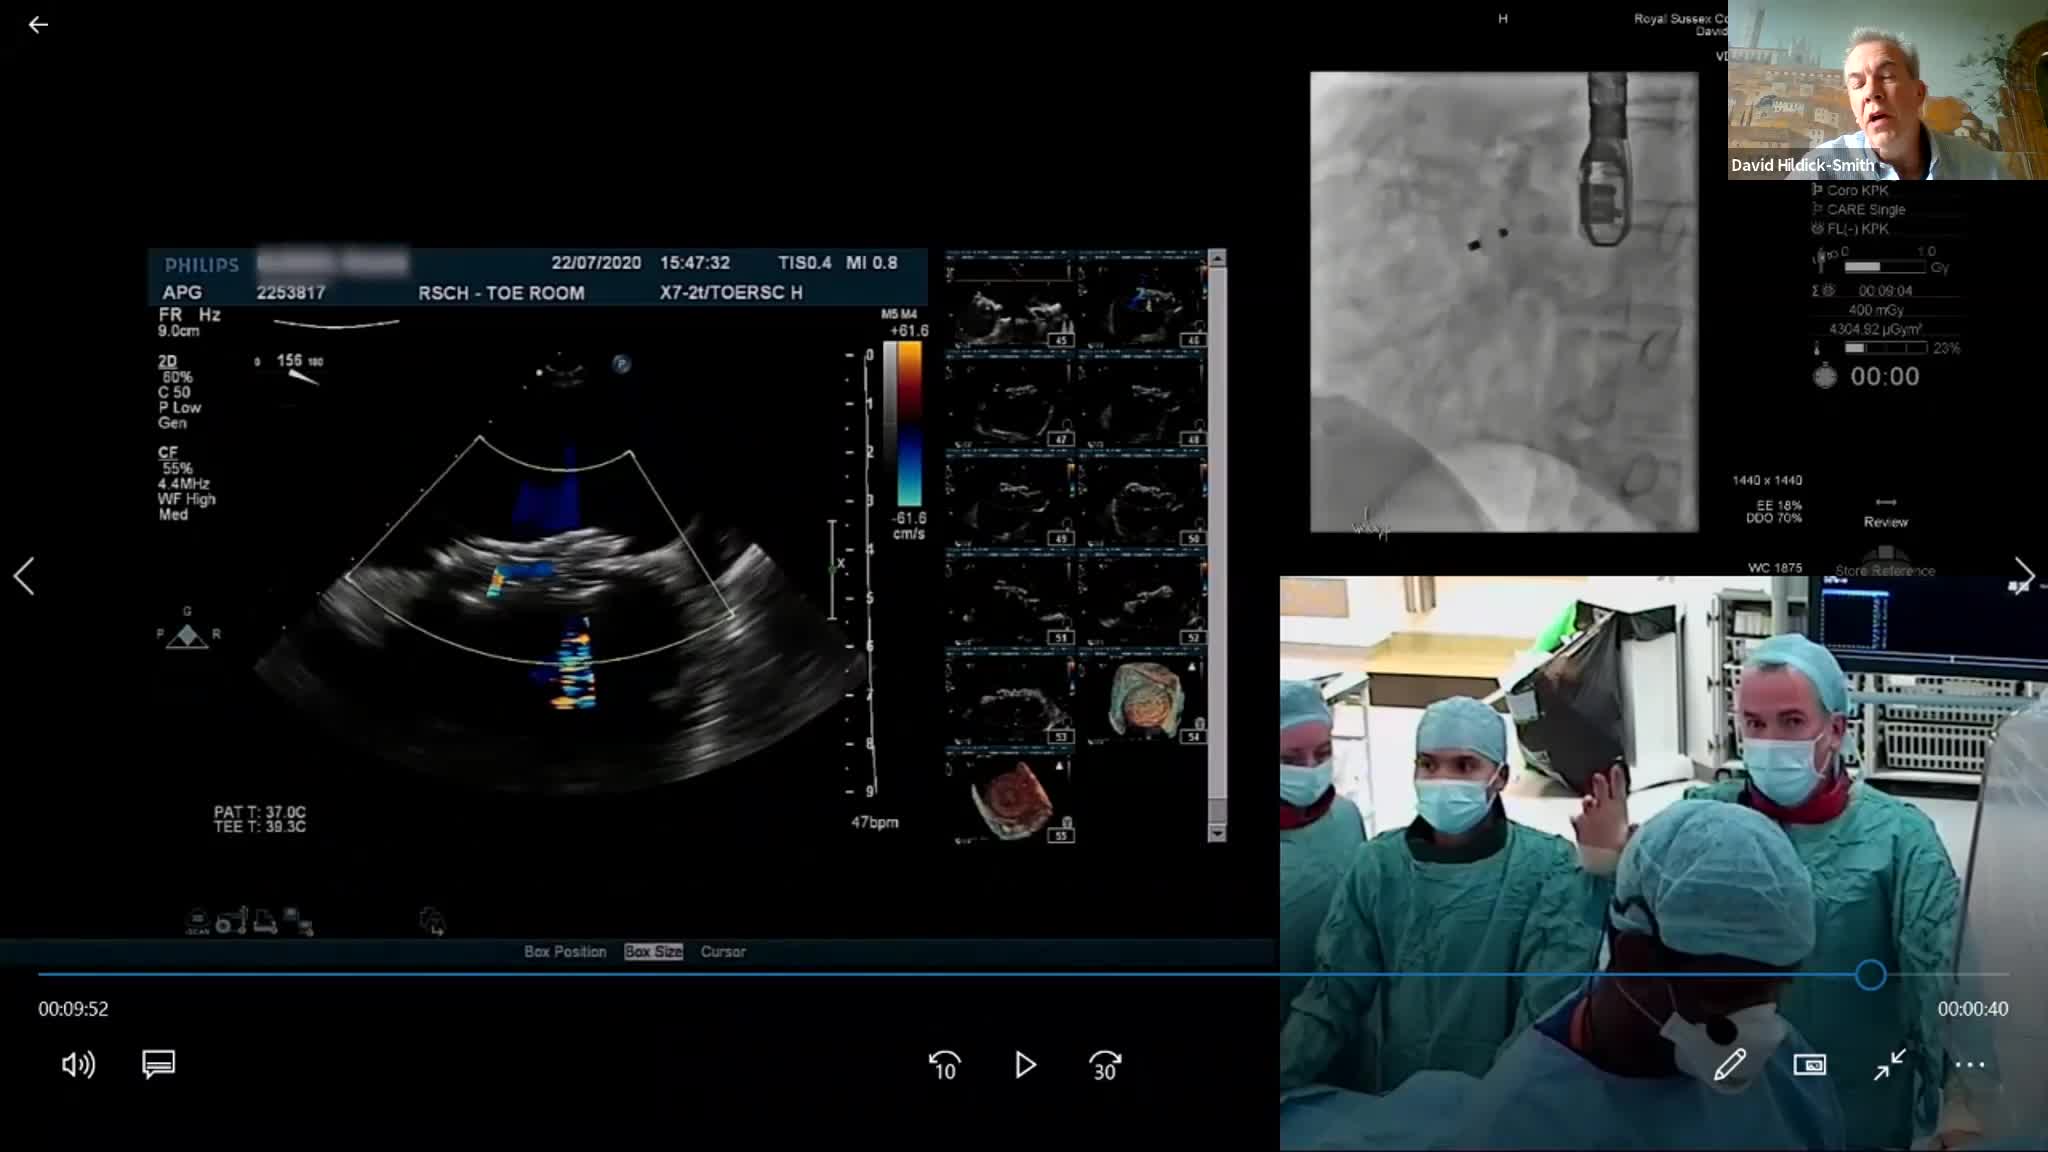

CSI CATHLAB LIVE - VSD CLOSURE WITH THE NEW OCCLUTECH PMVSD OCCLUDER (ANTEGRADE APPROACH)

CSI CATHLAB LIVE - INTER-ATRIAL SHUNT FOR DECOMPRESSION OF THE LEFT ATRIUM IN A PATIENT WITH VERY SEVERE HEART FAILURE WITH THE AFR DEVICE